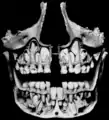

Crânio visto de frente

Dentes decíduos, erupção dos permanentes.

Dentes, e seio maxilar.